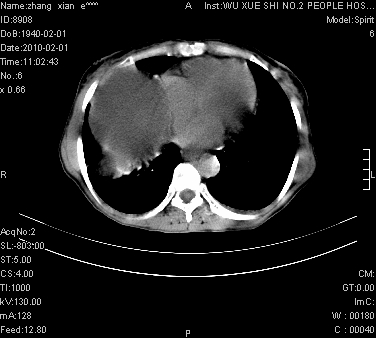

标题: CT24434:70岁 女 腹胀,腹水原因待查 [打印本页]

标题: CT24434:70岁 女 腹胀,腹水原因待查

大量腹水,脾囊肿可能性大,建议增强

大量腹水,右肾、脾囊肿可能性大          考虑左侧附件区占位,建议增强